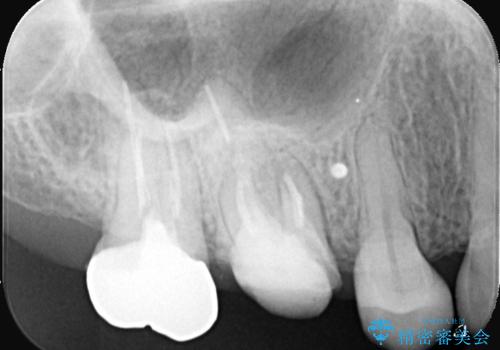

歯と歯の間の虫歯もセラミックで再発防止

担当医 河口智英